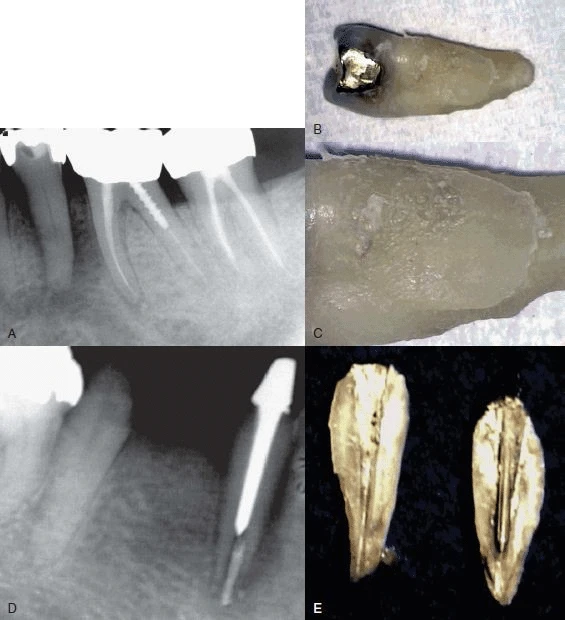

Hình 9. Đôi khi không có dấu hiệu rõ ràng cho thấy lý do răng có triệu chứng. (A) Hình ảnh X quang cho thấy răng cối lớn thứ hai hàm dưới có miếng trám sâu mức độ trung bình. (B) Thử tuỷ cho thấy răng chết tuỷ. Không chiếu sáng nên không thấy có đường nứt nào cả. (C) Chiếu ánh sáng có cường độ cao lên bề mặt răng, quan sát thấy vết nứt ở mặt ngoài. (D) Chiếu sáng vào mặt xa – trong của răng.